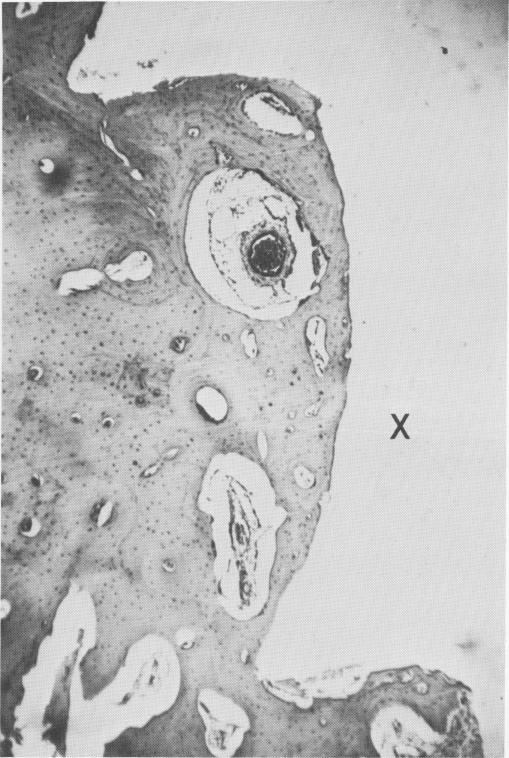

Fig. 4-72. The most obvious difference between a metallic and a crystalline implant was the presence or absence of a connective tissue membrane. In this photomicrograph of a bone section around a crystalline implant site (X), there is no fibrous tissue membrane. (Courtesy K. R. Blakey, Howard University.)

1 Bone section around a crystalline endosseous implant site